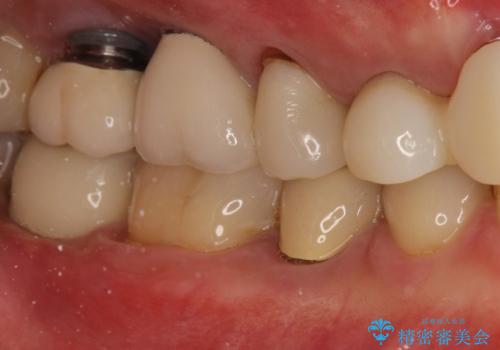

右下の奥歯を抜歯 インプラント治療による咬合回復

精査すると保存が難しいため抜歯をして、インプラントを埋入、かぶせ物を装着する計画としました。

インプラント治療により、周りの歯を削ることなく咬合を回復することができました。